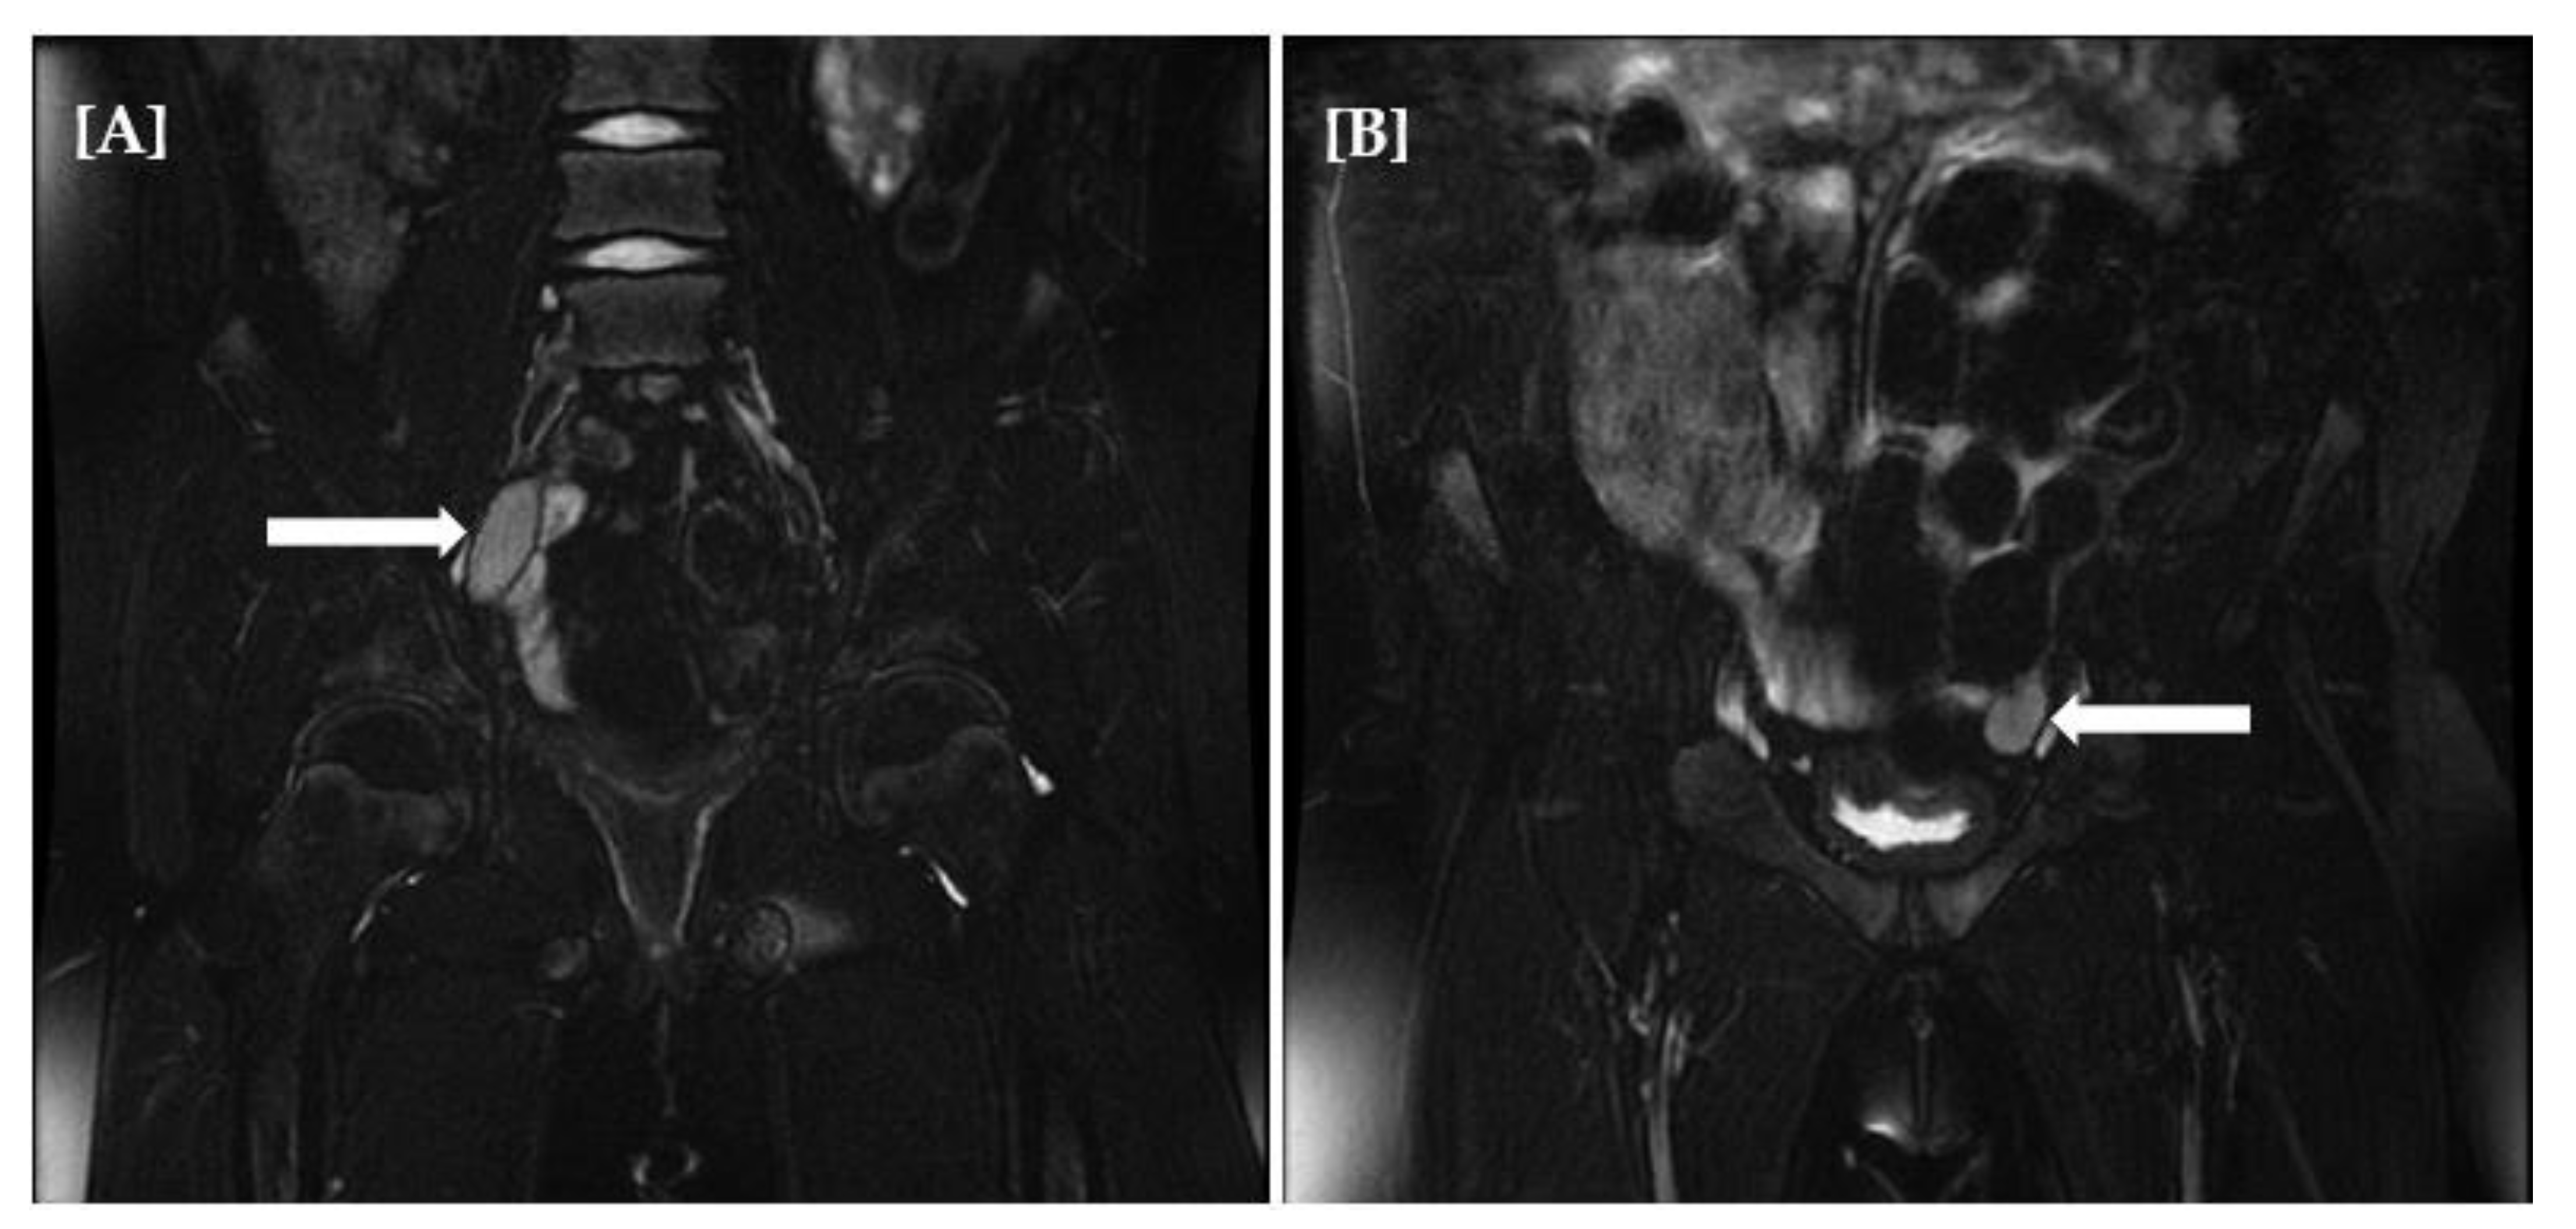

Currently, a 17-year-old girl delivered full-term (G2P2, parents unrelated) with normal birth parameters was diagnosed with adrenal failure in the first year of life. Family history of autoimmune diseases was negative. Hyperpigmentation of the skin was reported when she was ~1 month old. At the age of 10 months, the child had an acute adrenal crisis with a classic symptomatology (vomiting, dehydration, weight loss, hypotension, and electrolyte disturbances). Hormonal tests revealed primary adrenocortical insufficiency, and steroid profiles showed lack of products of steroidogenesis. Classical replacement therapy with hydrocortisone and fludrocortisone has been implemented. In January 2014, the girl was admitted to the clinic to assess the effectiveness of the current doses of medication used. Physical examination demonstrated skin hyperpigmentation, obesity, puberty Tanner I, and female external genitalia. In the absence of puberty symptoms, elevated LH level (26.5 mIU/mL) with either pre-pubertal FSH and estradiol level (4.9 mIU/mL and 28 pmol/L, respectively) was a warning. Moreover, undetectable or very low levels of testosterone (<2.5 ng/mL), DHEAS (<15 µg/dL), and 17-OH progesterone (0.59 ng/mL) were noted. In the repeated steroid profile, apart from metabolites derived from substitution therapy, no other steroidogenesis markers were found. Despite adequate hydrocortisone supply, ACTH levels (4961 pg/mL) were still very high. However, before the admission to the our department, the patient was treated for 11 years in the different center. Magnetic resonance imaging (MRI) of hypophysis did not reveal either hypophysis enlargement or adenoma. In the pelvic ultrasound, the uterus and ovaries were not visualized. A cytogenetic study, by karyotyping with routine G-banding according to the recommendations of the American College of Medical Genetics, revealed a 46,XY karyotype. Magnetic resonance imaging (MRI) confirmed the presence of gonads in the abdomen and the absence of the structures derived from the Müllerian ducts (Figure 2A,B). Based on the clinical picture and the results of additional tests, the STAR or CYP11A1 gene mutation with disorder of sex determination 46,XY karyotype gonadal dysgenesis with adrenal failure was taken into account. In June 2014, the patient was subjected to bilateral laparoscopic gonadectomy. Histopathological examination confirmed a typical testicular tissue with neither gonadal dysgenesis nor lipid storage features. This finding explains the discrepancy in the levels of gonadotrophins in our patient described above. High LH level was related to the lack of testosterone production with no negative feedback and normal FSH level was related to the preserved Sertoli cells function and normal production of inhibin b. A molecular examination was performed to confirm the diagnosis—two variants in the cholesterol side-chain cleavage enzyme gene CYP11A were identified. Patient, based on the psychological tests and consultation presents female gender identity and behavior and in follow-up care, estrogen replacement therapy was implemented in July 2014 with continuation of hydrocortisone and fludrocortisone supplementation.

Figure 2.

Magnetic resonance imaging (MRI) of abdomen and pelvis minor showing presence of gonads (right (A), left (B)) with the absence of the structures derived from the Müllerian ducts.